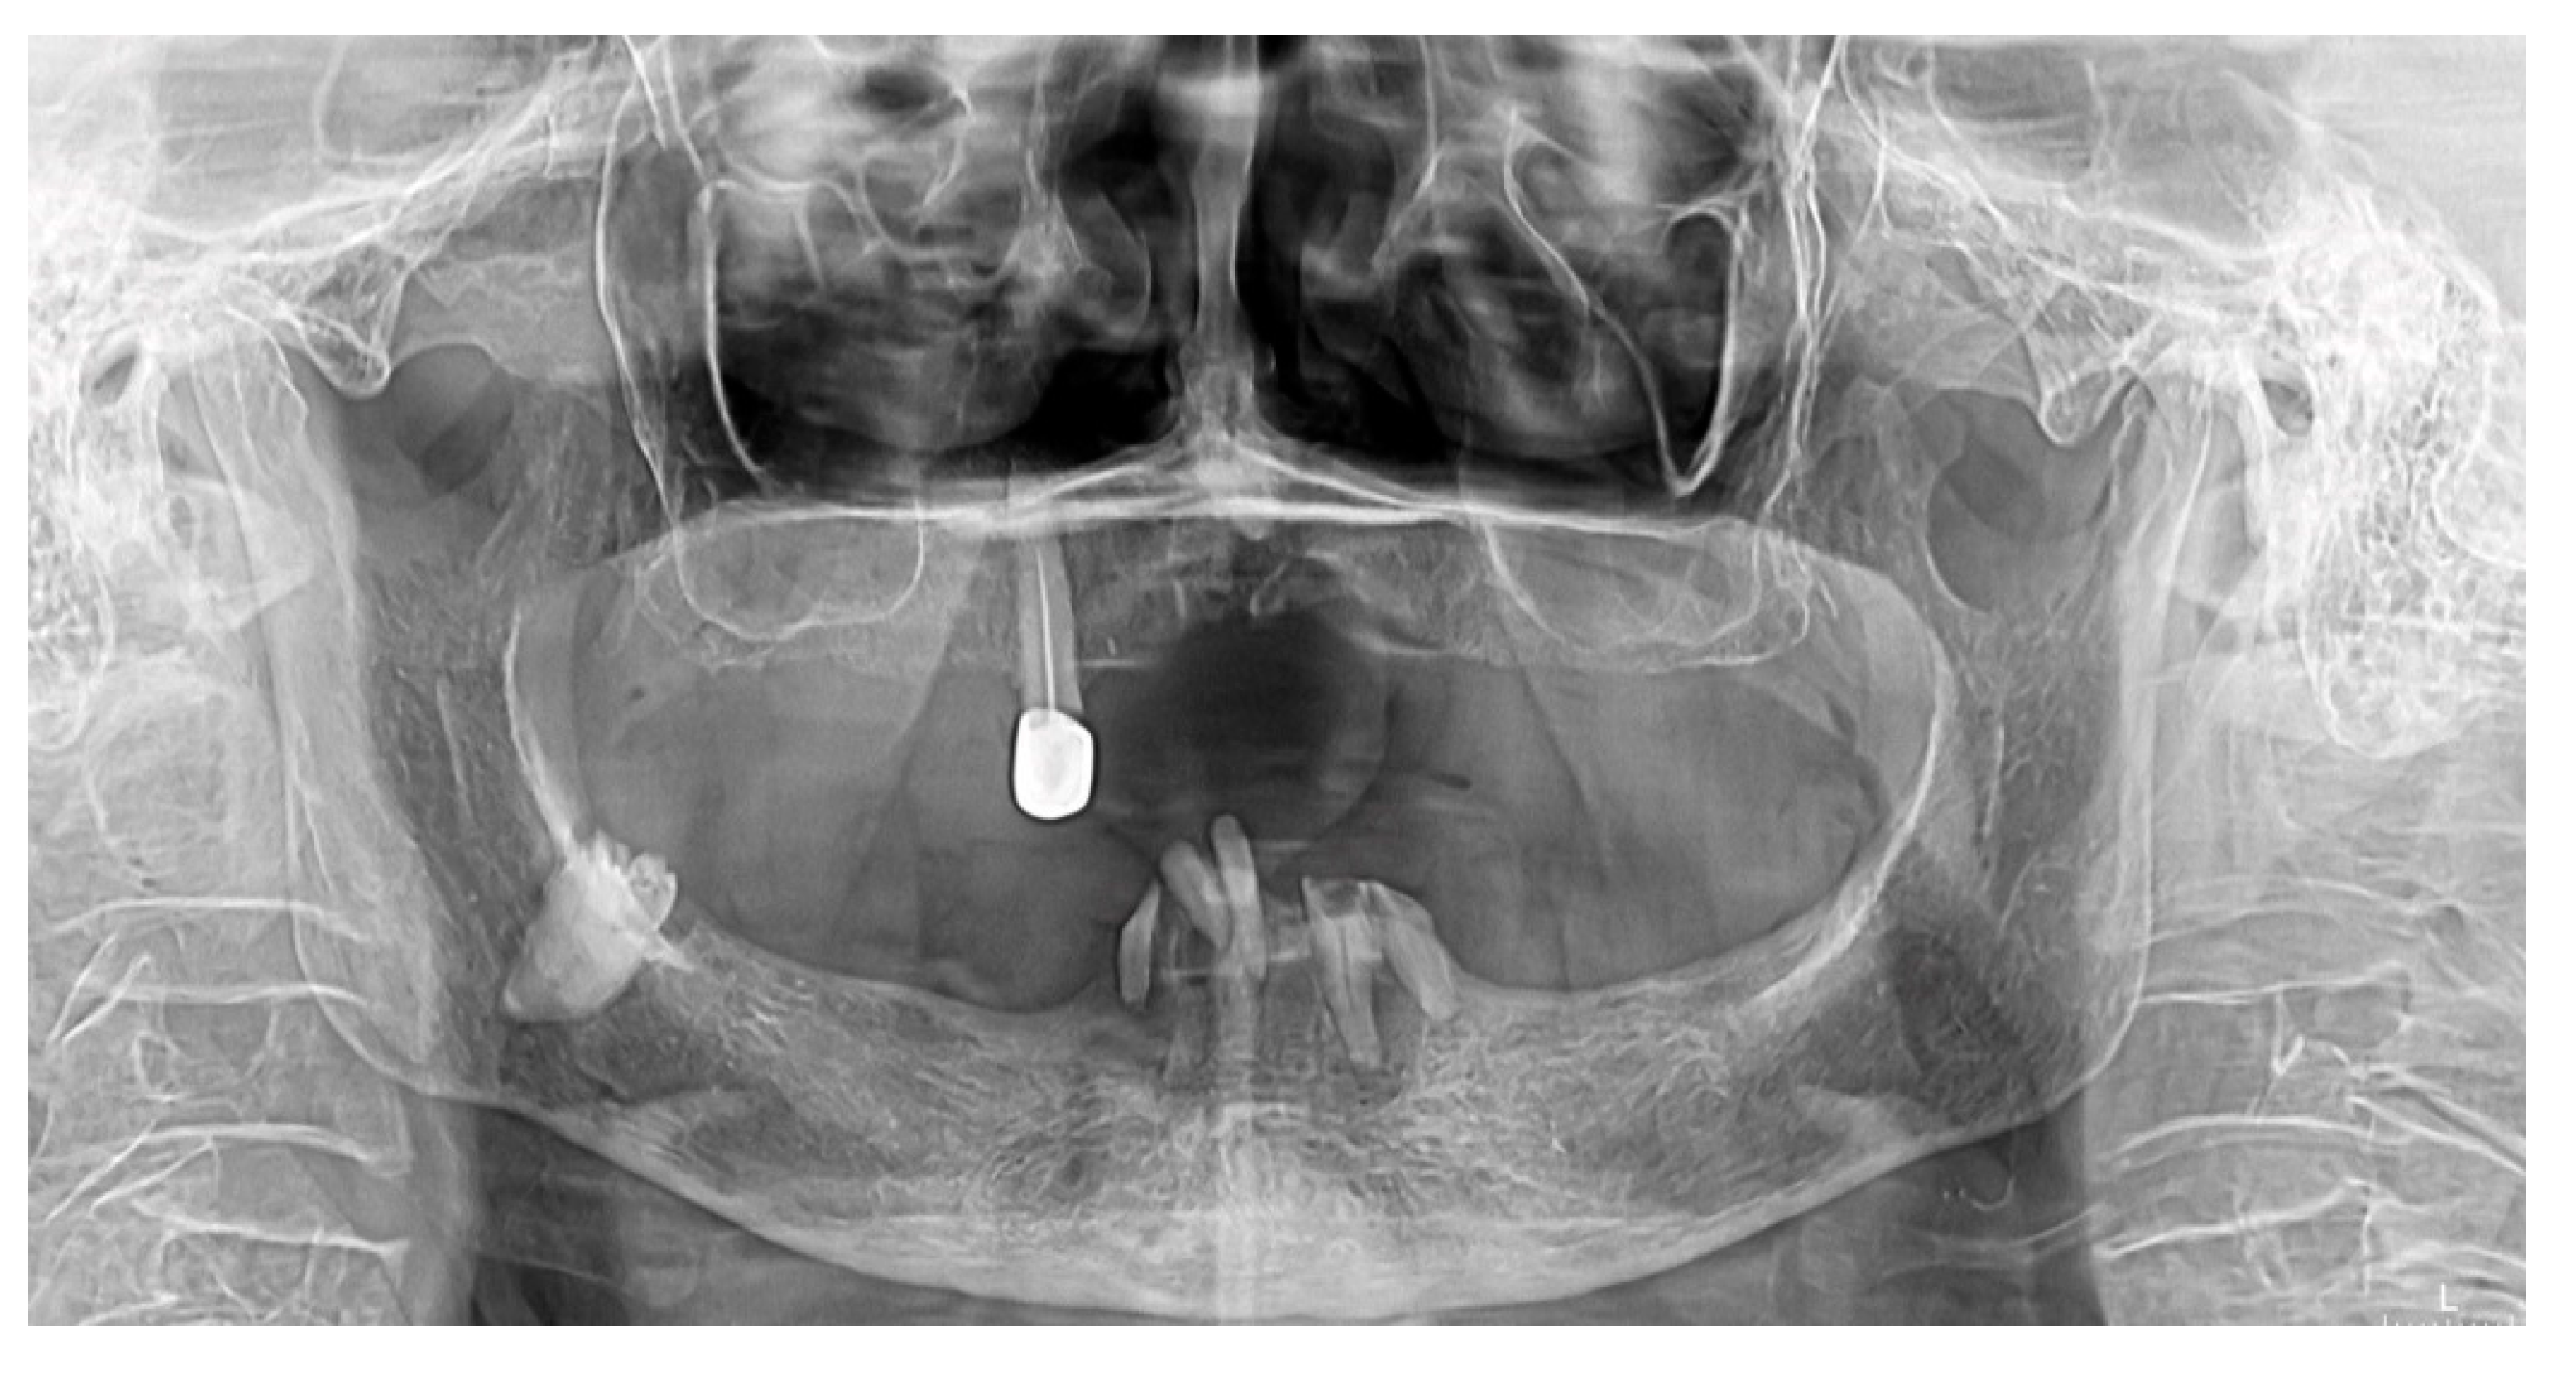

Diagnostic Aspects of an Included Third Molar in an 88-Year-Old Patient: A Case Report and Literature Review

2. Case Report

- the patient was referred for a panoramic radiography;